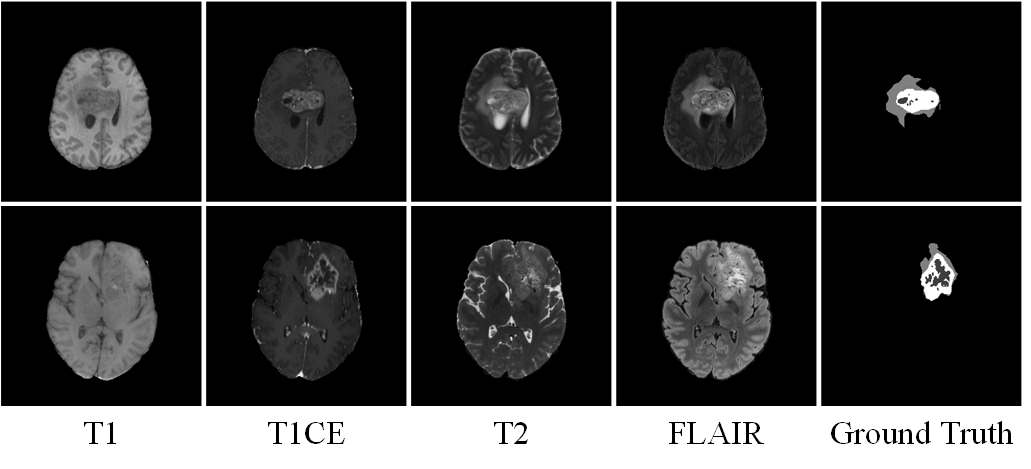

二、脑肿瘤分割

脑肿瘤是一种高度侵袭性和恶性的神经系统肿瘤,对患者的身心健康构成严重威胁。由于其复杂性,通常在晚期才被发现,从而使临床治疗变得极为困难。因此,早期诊断脑肿瘤至关重要。在临床上,磁共振成像(MRI)是检测和诊断脑肿瘤的首选手段。MRI包括四种成像方式:液体衰减反转恢复(FLAIR)、T2加权(T2)、T1加权(T1)和T1增强(T1CE),提供了关于脑组织结构和病变的不同信息。通过MRI对脑肿瘤进行分割,可以帮助放射科医生更准确地识别和定位肿瘤组织,从而更好地规划手术和监测治疗。然而,放射科医生在MRI上进行脑肿瘤分割是一项费力且主观的任务,常常导致注释的不确定性。因此,亟需设计有效、可靠的脑肿瘤自动分割(BraTS)方法,以减轻放射科医生的工作负担并提高分割准确率。

图3 MRI四种成像方式以及脑肿瘤分割的样例